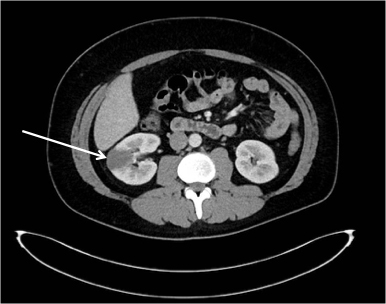

A CT abdomen with contrast (Fig. 1) again demonstrated uncomplicated sigmoid diverticulosis but did not identify a gastrointestinal cause of bleeding. It also showed multiple right renal infarcts suspicious for septic emboli. On subsequent assessment, the patient had a pansystolic murmur loudest at the apex and splinter haemorrhages present in two fingernails.

Fig. 1.

CT abdomen with contrast. A CT abdomen with contrast was performed which demonstrated a right renal infarct (white arrow) and uncomplicated sigmoid diverticulosis. No cause for gastrointestinal bleeding was identified. CT, computed tomography.